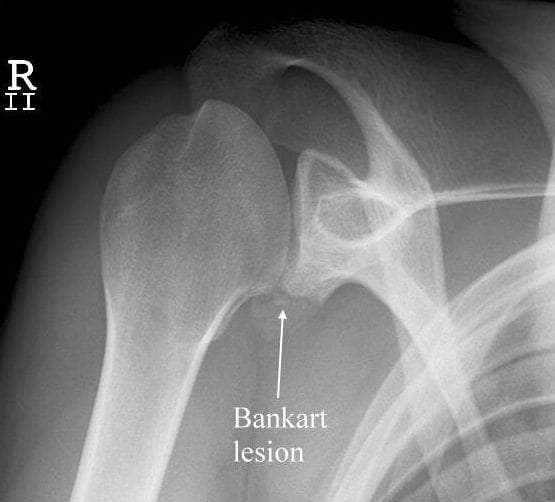

What Is Shoulder Bankart Repair . Minimally invasive surgical procedure to repair a tear of the glenoid labrum in the shoulder. This is a bankart lesion. A bankart repair procedure is sometimes necessary to treat shoulder instability. When your shoulder bone is forced out of its socket and into the glenoid labrum, it can tear it or even separate it from the bone. The bankart repair procedure, named after british surgeon arthur bankart, is a surgical technique that fixes recurrent shoulder dislocations by reattaching lax ligaments to. The labral tear surgery aims to repair and tighten overstretched and damaged. A bankart lesion repair is usually carried out arthroscopically (hey hole surgery) under general anaesthetic. Typically, it is indicated when a bankart lesion exists and the injury is in a. A bankart repair is a surgical procedure to prevent recurring anterior shoulder dislocations due to.

A bankart repair is a surgical procedure to prevent recurring anterior shoulder dislocations due to. A bankart repair procedure is sometimes necessary to treat shoulder instability. Typically, it is indicated when a bankart lesion exists and the injury is in a. The bankart repair procedure, named after british surgeon arthur bankart, is a surgical technique that fixes recurrent shoulder dislocations by reattaching lax ligaments to. Minimally invasive surgical procedure to repair a tear of the glenoid labrum in the shoulder. This is a bankart lesion. When your shoulder bone is forced out of its socket and into the glenoid labrum, it can tear it or even separate it from the bone. The labral tear surgery aims to repair and tighten overstretched and damaged. A bankart lesion repair is usually carried out arthroscopically (hey hole surgery) under general anaesthetic.

What Is Shoulder Bankart Repair When your shoulder bone is forced out of its socket and into the glenoid labrum, it can tear it or even separate it from the bone. The bankart repair procedure, named after british surgeon arthur bankart, is a surgical technique that fixes recurrent shoulder dislocations by reattaching lax ligaments to. This is a bankart lesion. A bankart repair procedure is sometimes necessary to treat shoulder instability. Typically, it is indicated when a bankart lesion exists and the injury is in a. The labral tear surgery aims to repair and tighten overstretched and damaged. A bankart lesion repair is usually carried out arthroscopically (hey hole surgery) under general anaesthetic. A bankart repair is a surgical procedure to prevent recurring anterior shoulder dislocations due to. Minimally invasive surgical procedure to repair a tear of the glenoid labrum in the shoulder. When your shoulder bone is forced out of its socket and into the glenoid labrum, it can tear it or even separate it from the bone.